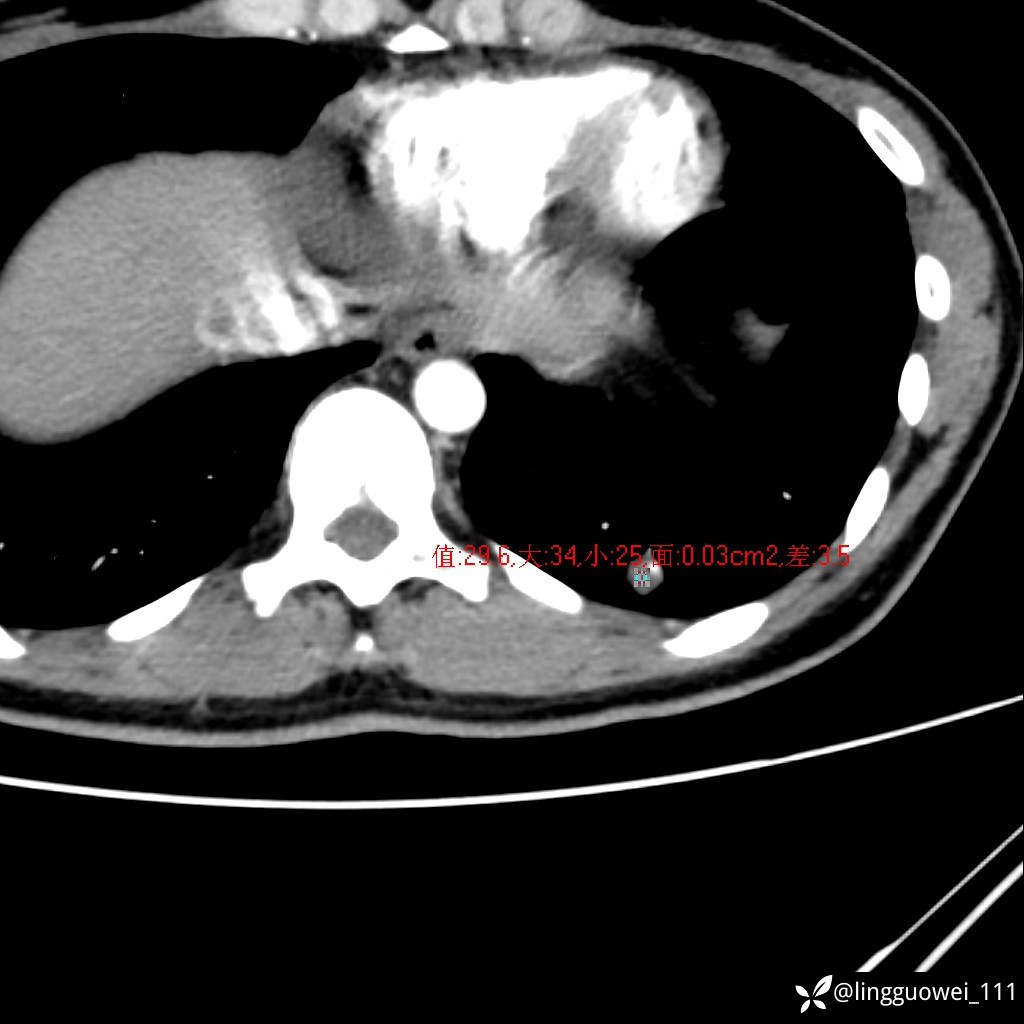

年轻女性咳嗽,CT发现肺结节,良性还是恶性?(4天后公布结果)

患者性别:女

患者年龄:26岁

主诉:咳嗽来诊,结节性质不明。

肺毛细血管瘤 (2)